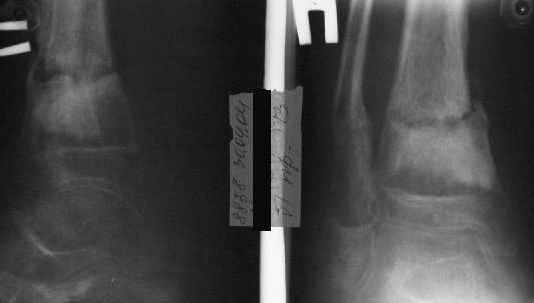

Фиксация

|

в гипсе

Промежуточный

A> В январе 2005: варусная деформация н\3 голени,

A> Операции: 1 Клиновидная резекция на вершине деформации м\берцовой кости.

A> 2 Тугоподвижный ложный сустав н\3 б\берцовой кости.